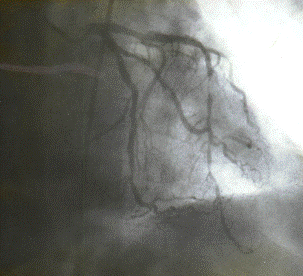

2.3.5 Коронароангиография (КГ), вентрикулография (ВГ)

Коронарографическое исследование проводили на ангиографических установках "Angioscope D" фирмы "Siemens" (Германия), "Integris 3000" фирмы "Philips" (Голландия) по методу М. Judkins и Sones. Для контрастирования КА использовали омнипак 300-350. КГ ЛКА выполняли в стандартных проекциях по методике Gensini: правая косая 150 и 450, левая косая проекция 600, левая боковая 900. В некоторых случаях использовали дополнительные проекции: левая передняя косая 450-750, каудокраниальная 300.КГ ПКА выполняли в стандартных проекциях: правой косой 450, левой косой 600, левой боковой 900 от сагиттальной оси. Анализ коронарограмм осуществляли на просмотровом аппарате "Tagarno 35AX". При анализе коронарограмм определяли тип кровоснабжения сердца, состояние основного ствола ЛКА, степень и уровень поражения коронарных артерий, диаметр коронарных артерий, количество пораженных артерий, наличие коллатерального кровотока.